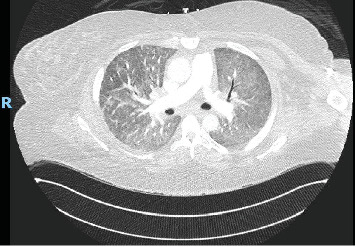

Background: Diffuse alveolar hemorrhage (DAH) is a potentially life-threatening condition which can present with hemoptysis, diffuse alveolar infiltrates, anemia, and hypoxic respiratory failure. Antisynthetase syndrome (AS) is a rare autoimmune disorder most often characterized by nonerosive arthritis, proximal muscle weakness with elevated muscle enzymes, Raynaud's phenomenon, hyperkeratosis of the digits (mechanic's hands), and interstitial lung disease. According to large population studies, AS has an annual incidence of 0.56 per 100,000 persons and prevalence of 9 per 100,000. The most common autoantibody is anti-aminoacyl-transfer RNA synthetase for histidine (anti-Jo-1) with a reported prevalence of 20%-30%, whereas anti-Pl-7 (for threonine) accounts for less than 5% of all autoimmune myositis. Specific myositis autoantibodies determine clinical phenotype. PL-7 is characterized by interstitial lung disease, myositis, and arthritis. Autoimmune myositis, specifically AS, is a rare cause of DAH. Herein, we describe the first reported case of PL-7-associated AS with DAH. Case Presentation: A 41-year-old female presented with worsening shortness of breath and hemoptysis. Laboratory studies included a hemoglobin of 10.5 g/dL, mildly elevated liver enzymes, and a creatine phosphokinase (CPK) of nearly 4000 U/L. CT of the chest showed diffuse ground glass opacities bilaterally. Serial aliquots of the bronchoalveolar lavage (BAL) fluid revealed progressively hemorrhagic return and histopathologic analysis consistent with DAH. Other concurrent causes of DAH were ruled out. Conclusion: Although rare, AS should be considered a cause of DAH, particularly in patients presenting with symptoms of muscle weakness and arthritis or with evidence of mechanic's hands.

Abstract Image